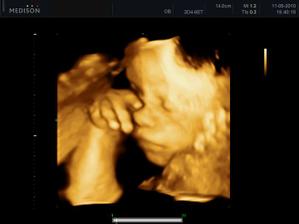

27.04. - (24+5) video, tak z videa nakonec sešlo. Dohodli jsme se s panem doktorem, že se mu ozvu, tak za 14 dní, až Karolínka ještě povyroste. Teď má v bříšku ještě moc místa a nebylo by to úplně ono. Tak jsme alespoň dostali několik foteček a dva doktoři nám potvrdili, že jde skutečně o holčičku.

11.05. - (26+5) dnes jedeme na video

video se povedlo, máme asi 6 cca 5 - 10ti vteřinových videíí.Bylo to super. Karolínka se zase mlela jako drak. Je taková živoučká 😀